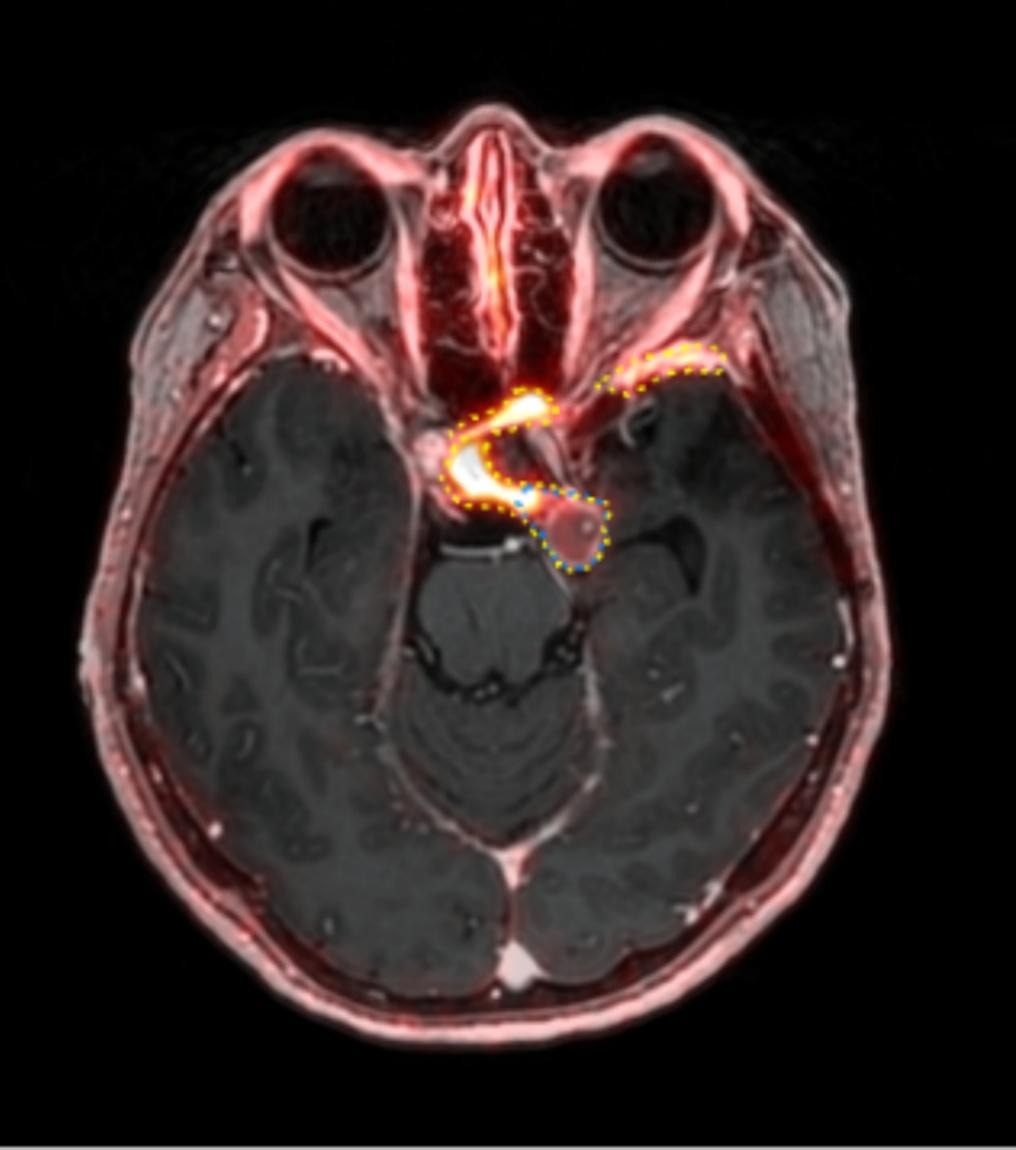

Dr. Jeffrey Olsen and colleagues at Washington University in St. Louis assessed the aftereffects of postoperative pelvic intensity-modulated radiation therapy (IMRT) with and without chemotherapy for women with endometrial or cervical cancer.

"The treatment planning goal was to cover the tissue at risk for recurrence, while minimizing the radiation dose to the bladder, bowel, and bone marrow," Olsen said.